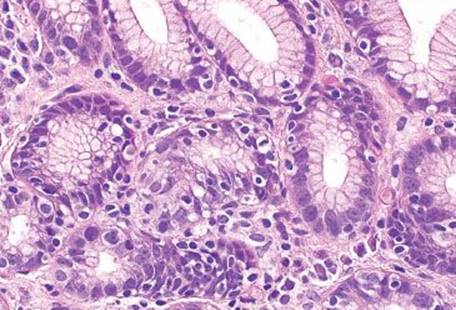

Figure 2.141 Lymphocytic gastritis pattern, lymphoepithelial lesion, mucosa associated lymphoid tissue (MALT) lymphoma. These gastric glands have been damaged by intraepithelial lymphocytes. This pattern of injury is termed lymphoepithelial lesion (LEL), composed of three or more lymphocytes within the gland epithelium. Note the smaller gland that has been almost entirely obliterated by these LELs (arrowhead), and the background intense lymphocytic infiltrate in the lamina propria. By comparison, lymphocytic gastritis is composed of a mixed inflammatory infiltrate in the lamina propria and single, scattered intraepithelial lymphocytes.